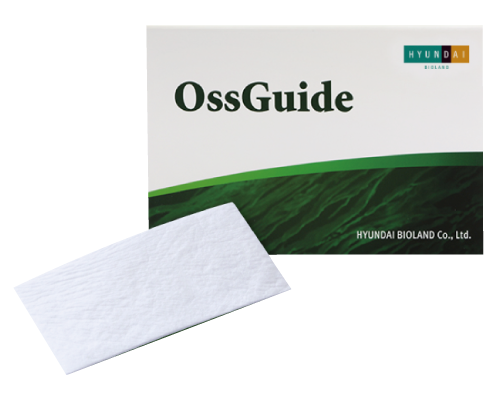

Absorbable Collagen Membrane

Size (mm)

15*20mm / 20*30mm

OssGuide is an absorbable dental membrane for guided bone regeneration

made of purified collagen without cross-linking or chemical treatment.

made of purified collagen without cross-linking or chemical treatment.

Absorbable Collagen Membrane

Size (mm)

15*20mm / 20*30mm

OssGuide is an absorbable dental membrane for guided bone regeneration

made of purified collagen without cross-linking or chemical treatment.

made of purified collagen without cross-linking or chemical treatment.

Better Stability

OssGuide functions as barrier to provide the prolonged

space maintenance with the long resorption period.

OssGuide is biodegradable and absorbed

within 24 weeks after implantation.

space maintenance with the long resorption period.

OssGuide is biodegradable and absorbed

within 24 weeks after implantation.

Better Tissue Integration

OssGuide has high porosity and specific surface area,

which support excellent blood supply.

This ensures optimal regeneration of bone and soft tissue.

which support excellent blood supply.

This ensures optimal regeneration of bone and soft tissue.

Better Stability

OssGuide functions as barrier to provide the prolonged

space maintenance with the long resorption period.

OssGuide is biodegradable and absorbed

within 24 weeks after implantation.

space maintenance with the long resorption period.

OssGuide is biodegradable and absorbed

within 24 weeks after implantation.

Better Tissue Integration

OssGuide has high porosity and specific surface area,

which support excellent blood supply.

This ensures optimal regeneration of bone and soft tissue.

which support excellent blood supply.

This ensures optimal regeneration of bone and soft tissue.